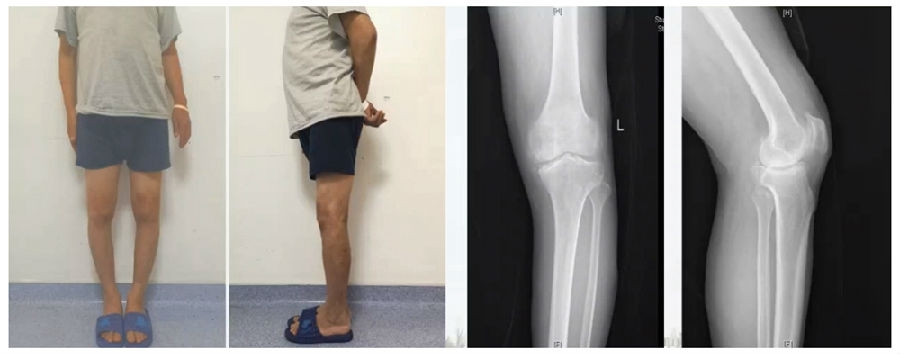

典型病例,男性,65岁,农民,双膝内翻16度。

术前影像

第一次为该患者做了传统上行开放截骨,撑开角度较大,术后用三种方法测量髌骨高度,发现髌骨高度受到影响,髌骨变低了。

左膝上行OWHTO(初次)

上行OWHTO髌骨高度测量

ISI法测量髌骨无明显变化;CDIBPI法测量髌骨降低明显;患者屈膝锻炼困难。

第二次来院做另一侧肢体时,采用下行截骨,术后患者髌骨高度,无论用哪种方法测量都无明显变化,而且患者膝关节功能迅速得到恢复。

右膝下行OWHTO(再次)

下行OWHTO髌骨高度测量

ISI法测量髌骨无明显变化;CDIBPI法测量髌骨无明显变化;患者屈膝明显改善。